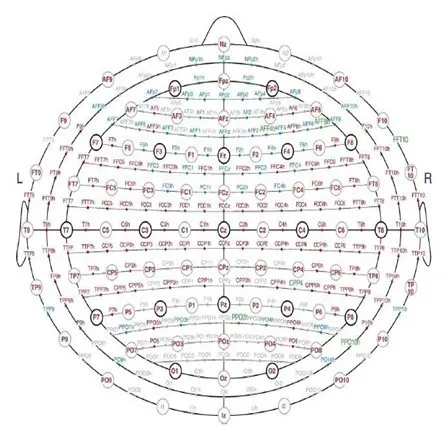

The numbers selected allowed for the additional electrodes to be placed in the coronal plane and have suitable designations (e.g. F2 placed between Fz and F4, and F6 placed between F4 and F8). Other additional electrodes included pharyngeal and cerebellar elelectrodes which were termed Pg, Pg2, Cb1, and Cb2, resspectively.

Fig. 7 Modified combinatorial nomenclature